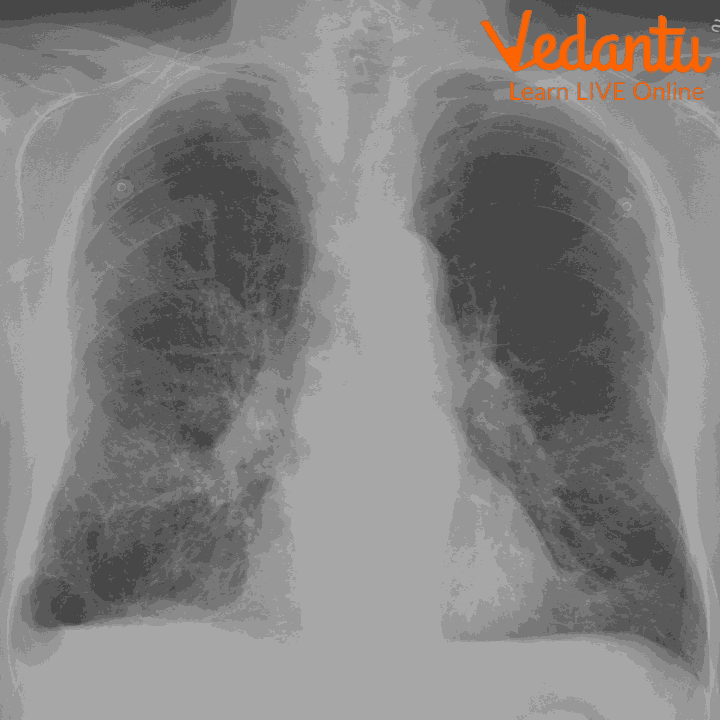

Chest x-ray

Firstly, the person is laid on an x-ray machine. The x-ray beam travels through the air and it comes in contact with the tissues of the body and then it produces an image on a metal film.

Soft tissues of the body like organs and skin cannot absorb the high velocity rays and the beam passes through them.

There are dense materials present inside our body for example bones, they can absorb the radiations of x-rays.

In the areas which are exposed to x-rays, they develop a film called x-rays film. White areas in the film show denser regions of the body for example bones which absorb x-rays and black areas on an x-ray show the soft tissues from which x-rays have not passed.